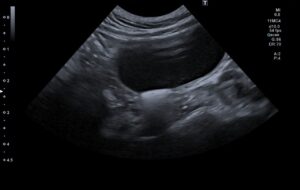

検査の結果、左の尿管結石と閉塞が見られました。

また、膀胱内にも結石が存在したため、同時に摘出することとしました。

術後のエコーで腎臓の腎盂拡張は改善されています。